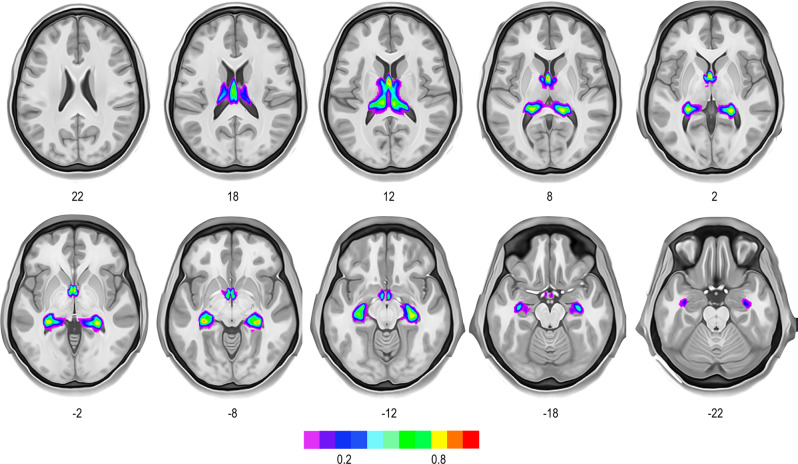

We successfully identified and mapped the fornix in all 178 participants (individual dissections are available from https://neurovault.org/collections/12108). Figure 1 provides a representative tractography reconstruction of the fornix and its adjacent commissural white matter tracts. We reliably identified the anterior and posterior columns of the fornix enclosing the anterior commissure, the body of the fornix underneath the corpus callosum, and the split of fornix into the crura fornicis at the posterior end of the corpus callosum (splenium). The crura arched around the thalami and continued as fimbriae along the medial temporal lobe to terminate in the hippocampi. Commissural fibers between the crura fornicis were, however, not evident. Figure 2 shows the fornix percentage overlay map. The full map is provided online (https://neurovault.org/collections/12108/). There was no evidence of a forniceal commissure.

Fig. 2. Percentage overlay map of the fornix for all 178 participants from the Human Connectome Project 7 T dataset.

The full percentage overlay map of the fornices is available online (https://neurovault.org/collections/12108/).

Virtual fiber dissection based on 7 Tesla diffusion-weighted imaging dataset of 178 participants did not identify interhemispheric connections between the crura fornicis. Previous tractography literature has been inconclusive about the visualization of a forniceal commissure: while some studies of the fornices did not describe commissural fibers30,32–34, others did describe a forniceal commissure31,35,37,38. Considering the spatial proximity between fibers of the splenium and the forniceal commissure, as histologically demonstrated in our study, there is a risk of misattributing splenial fibers as fibers of the forniceal commissure in tractography studies. The tractographic phenotype of the forniceal commissure in studies achieving putative detection31,35,37,38, resembles the visual appearance of rostrocaudal splenial fibers, but not that of histologically detected forniceal commissure fibers in our study. The absence of evidence in our study, however, might not be the evidence of absence. Previous reports indicated that fibers crossing the hemispheric midline have a different diameter39. In this case, the algorithm might not be able to trace commissural connections accurately. While the Human Connectome Project 7 Tesla data is a high-field high-resolution dataset offering high quality in vivo data (1 mm) for studying connectional anatomy in the living human brain, future studies might benefit from using submilimeter resolution datasets.

Percentage overlay maps

The resulting reconstructions were binarized and converted to fiber density maps to generate percentage overlay maps using an in-house matlab script (Matlab R2021b). Results were visualized with FSL (https://fsl.fmrib.ox.ac.uk/fsl/fslwiki/FSLeyes).